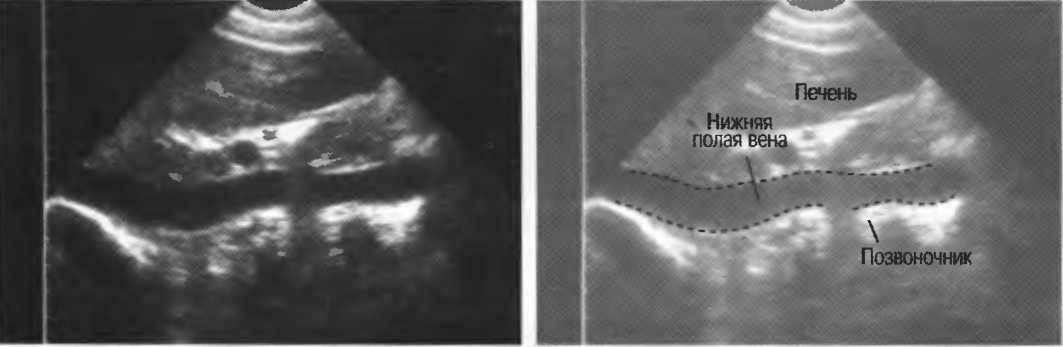

- Печеночные вены диаметром всего 3 мм должны визуализироваться при сканировании под углом 45° к поверхности нормальной печени (рис. 25).

Рис.25. Аппарат хорошего качества должен позволять визуализировать печеночные вены диаметром 3 мм. Этот тест может регулярно использоваться для контроля качества изображения.